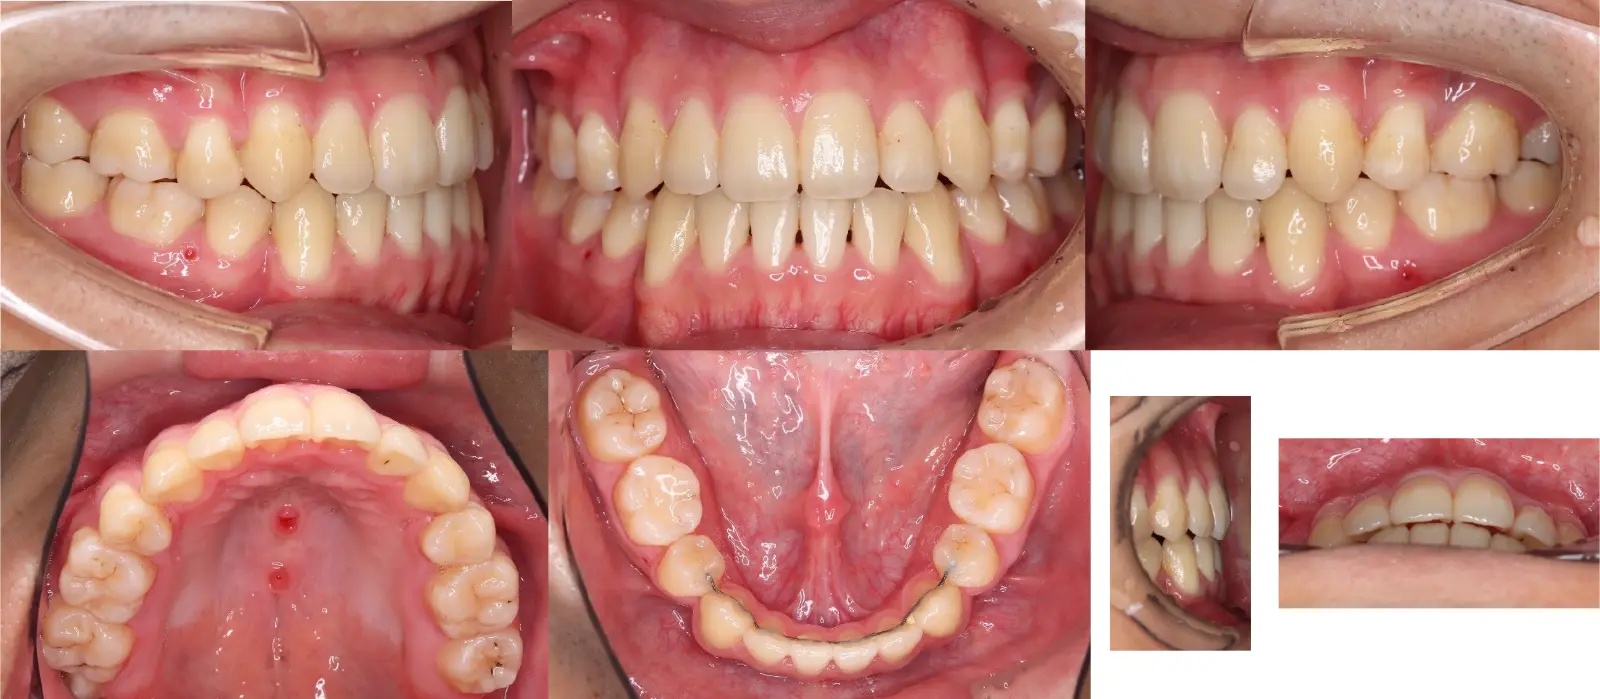

Angle Ⅱ級、叢生を伴う開咬

- 主訴

歯のガタガタ、前歯で噛めない

- 年齢

初診時10代

- 治療期間

36か月

- 治療回数

30回

- 治療に用いた主な装置

ハーフリンガル装置(Incognito&Alexander装置)、口蓋型歯科矯正用アンカースクリュー(i-station)

- 治療費

1,250,000円(税別)トータル料金

- 抜歯部位

上下顎第1小臼歯